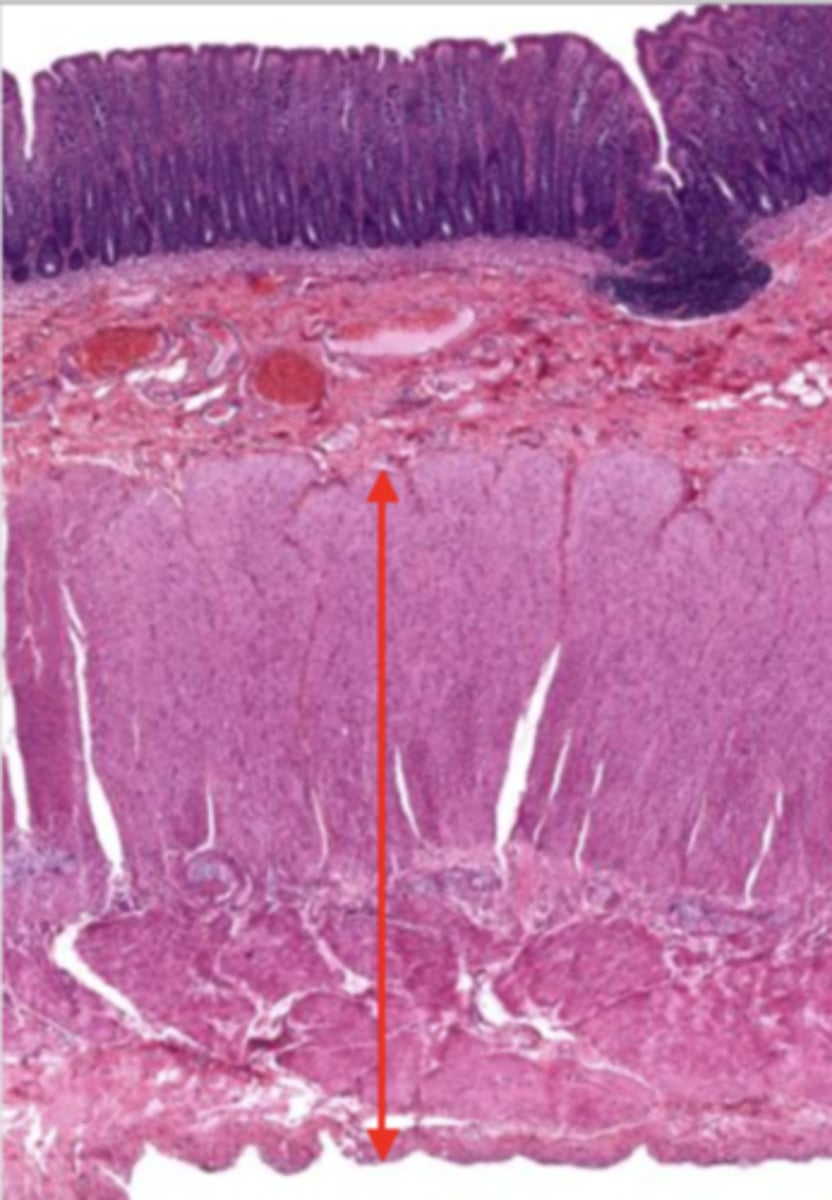

cardiac stomach (histology)

simple columnar epithelium

what kind of epithelium lines the mucosa of the cardiac stomach?

gastric pit (cardiac stomach)

lumen (cardiac stomach)

mucosa (cardiac stomach)

mucosal epithelium (cardiac stomach)

lamina propria (cardiac stomach)

muscularis mucosa (cardiac stomach)

submucosa (cardiac stomach)

contains glands and blood supply

muscularis externa (cardiac stomach)

serosa/adventitia (cardiac stomach)